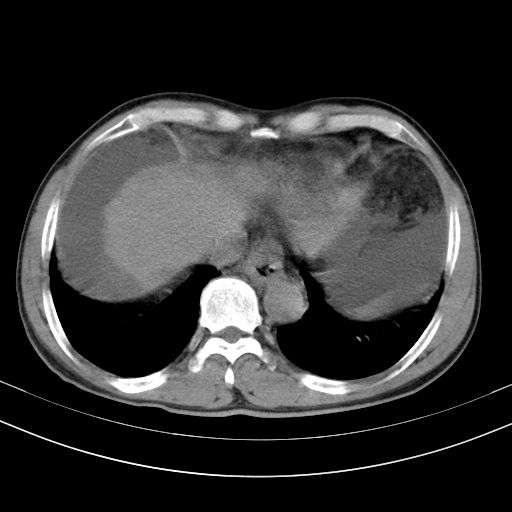

以下是引用随光逐影在2010-2-28 10:23:00的发言:[br]1)考虑肝癌;建议行ct增强扫描检查。2)肝硬化,脾大,腹水。3)慢性胆囊炎。